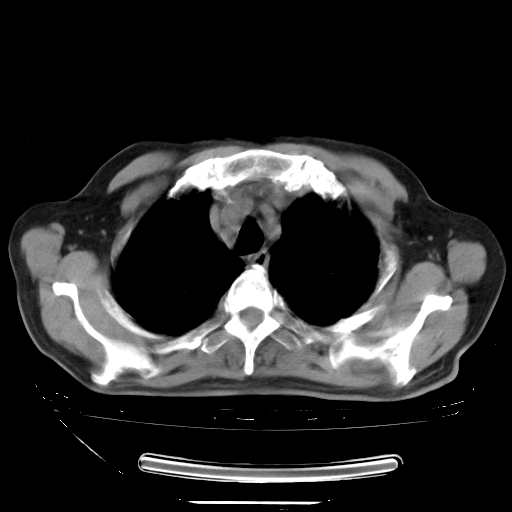

今天复查肺部CT,发现双肺广泛磨玻璃样改变。所以我把3月19日和5月9日相隔50天的肺部CT上传。请大家会诊。

5月9日肺部CT(在4月27日齐鲁医院肺部CT描述部分肺组织磨玻璃样改变,12天后肺组织广泛磨玻璃样改变)

2009年5月9日肺部CT

大致读了系列胸部CT:纵隔窗无明显异常,肺窗:从4、27至今:主要是双肺中下野外带可见毛玻璃样改变,目前处于急性肺泡炎阶段,至于原因考虑1、结替组织或胶原血管性疾病所致?2、恶性疾病如恶组在肺部所致的表现或细支气管肺泡癌?3、药物或其它原因如肺蛋白沉着症所致肺泡炎目前不太可能?总之,明天就去请我院的呼吸科、感染科、血液科和临免专家会诊哈。